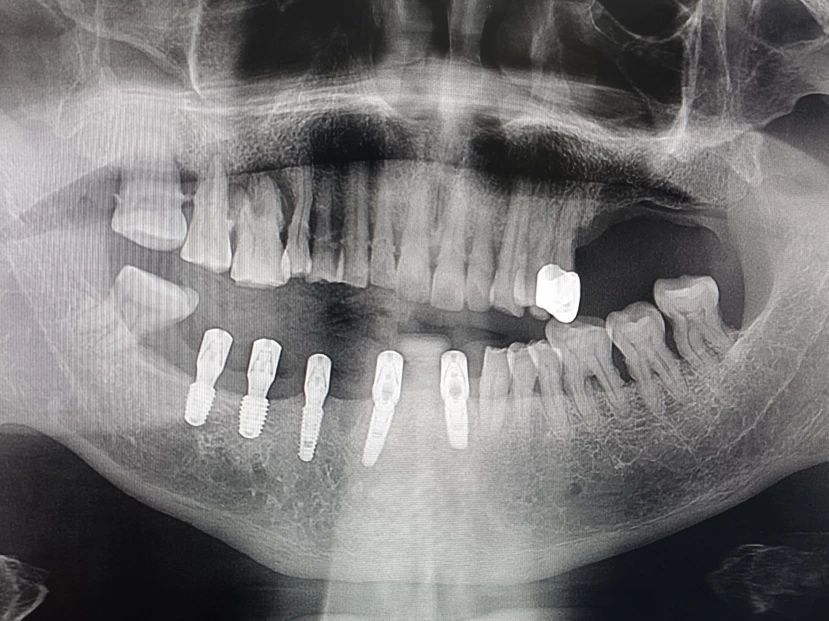

-下半口种植+即刻修复前-

-下半口种植+即刻修复中-

-下半口种植+即刻修复后-

-下半口种植+即刻修复前-

-下半口种植+即刻修复中-

-下半口种植+即刻修复后-